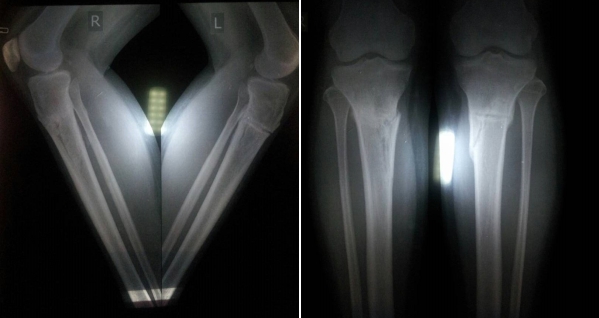

РЕНТГЕН ДО ОПЕРАЦИИ

Исходник - 34 года.

Дата операции 06.07.2017г.

Киргизия